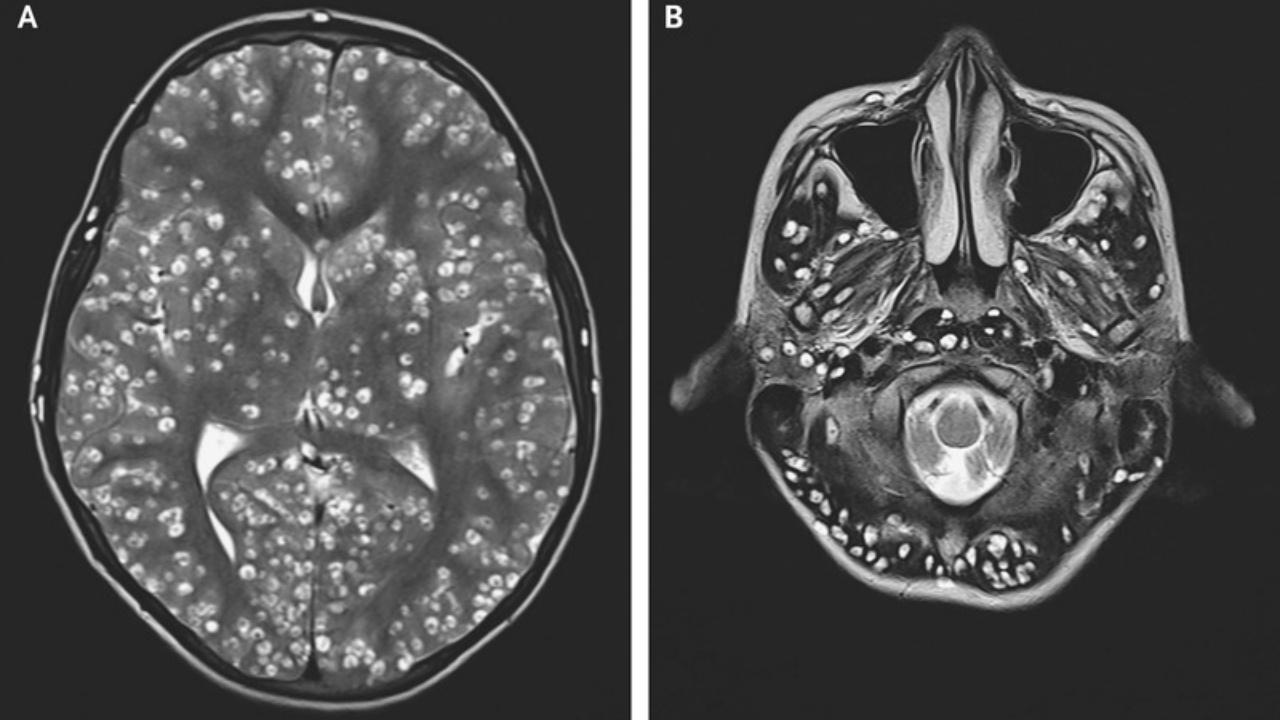

เพื่อให้รู้อาการของเขามากขึ้น แพทย์จึงทำการตรวจด้วยเครื่อง MRI และพบความเสียหายที่เกิดขึ้นโดย ซีสต์ (cysts) หรือถุงน้ำ ในเปลือกสมอง (cerebral cortex) และในก้านสมองซึ่งรวมถึงส่วนซีรีเบลลัม ซึ่งอยู่ด้านหลังศีรษะเหนือเส้นประสาทไขสันหลัง นอกจากนี้ แพทย์ยังพบซีสต์ในตาขวาและอัณฑะข้างขวาของคนไข้ด้วย

สิ่งที่พบทำให้แพทย์วินิจฉัยว่าชายคนนี้เป็นโรคจากไข่พยาธิตัวตืด อันเป็นโรคพยาธิในสมองที่เกิดจากการที่ คนกลืนไข่พยาธิตัวตืดที่อยู่ในอุจจาระของคนอื่นที่มีพยาธิในลำไส้ ตัวอ่อนของพยาธิจะออกมาจากไข่และเจาะเข้าไปในกล้ามเนื้อและเนื้อเยื่อสมอง และก่อให้เกิดซีสต์